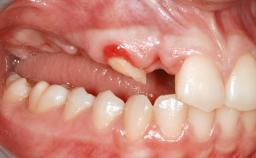

A 45-year-old woman with a completely edentulous maxilla was referred to evaluate the possibility of rehabilitation with an implant-supported prosthesis. This patient was healthy and a non-smoker. She had been wearing a maxillary complete denture opposing a natural mandibular dentition since her twenties. This situation had resulted in progressive resorption of the alveolar ridge, repeatedly creating a need for relining the denture. Twenty years later, despite multiple adaptations and the use of “glues” the denture was unstable and causing the patient psychological and functional discomfort.

Bone Volume Horizontally and vertically sufficient Horizontally deficient Deficient vertically or deficient vertically AND horizontally